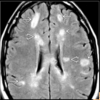

Which of the following sequences is the go to for identifying multiple sclerosis using an MRI scan? 1 - T1 axial no contrast 2 - T1 axial with contrast 3 - Flair with no contrast 4 - T2 with contrast

3 - Flair with no contrast - Gadolinium

When looking at an MRI, is the cerebrospinal fluid white on a T1 or T2 scan?

- T2 scan - CS appears white and bright Remember WW2 = Water is Whiter on T2 - MS lesions also appear bright

- periventricular - image shows bright demyelination plaques around the lateral ventricles